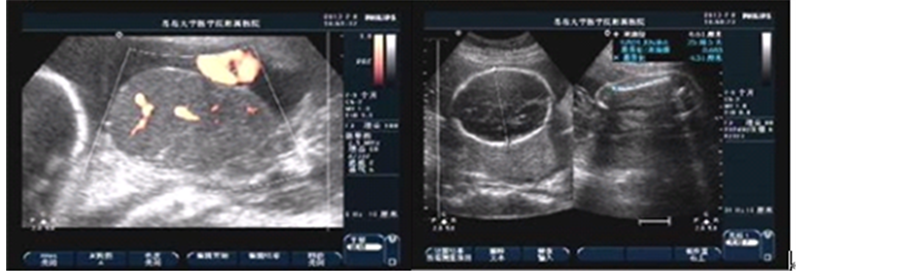

The mother was a 33-year-old yellow multipara with no significant antenatal history. There was no maternal fever and her complete blood count was normal. In the 24th week, a large chorioangioma measuring 7.9 × 5.5 × 5.7 cm could be readily identical prenatally by sonography as a well-circumscribed, solid mass. She wanted to give birth to this baby till full term and accepted suggestion of taking examination regularly. In the 30 + 4 gestational age, the mass enlarged much about 14.1 × 9.7 × 13.0 cm with generalized edema and hydropericardium of the foetus. Figures 1(a), Figures 1(b) show the foetus and the tumor. An emergency cesarean section was performed. The placenta weighs 1180 g and measures 20 × 15 × 3 cm. A well-circumscribed soft tissue mass bulging out of the placenta was seen measuring 15 × 10 × 13 cm. There was no sign of malignancy and the diagnosis after pathology was chorioangioma. Figures 1(c), Figures 1(d) show the microscopic picture of the chorioan-

Figure 1. (a) Sonography shows fetal right atrium, ventricle enlarged, and liquid dark area could be seen within the pericardium, depth of about 0.34 cm. Cephalic subcutaneous tissue thicken, about 0.79 cm. Fetal surface of placenta detected a well-circumscribed hypoechoic mass, measuring 14.1 × 9.7 × 13.0 cm on the right side in which the internal echo was uneven and many small pieces of high echo could be seen; (b) (CDFI) Abundant blood flow signal was observed in the chorioangioma; (c) and (d) Tumor consisted of excessive proliferated capillaries, vascular pericytes cells and interstitial collagen.

gioma.